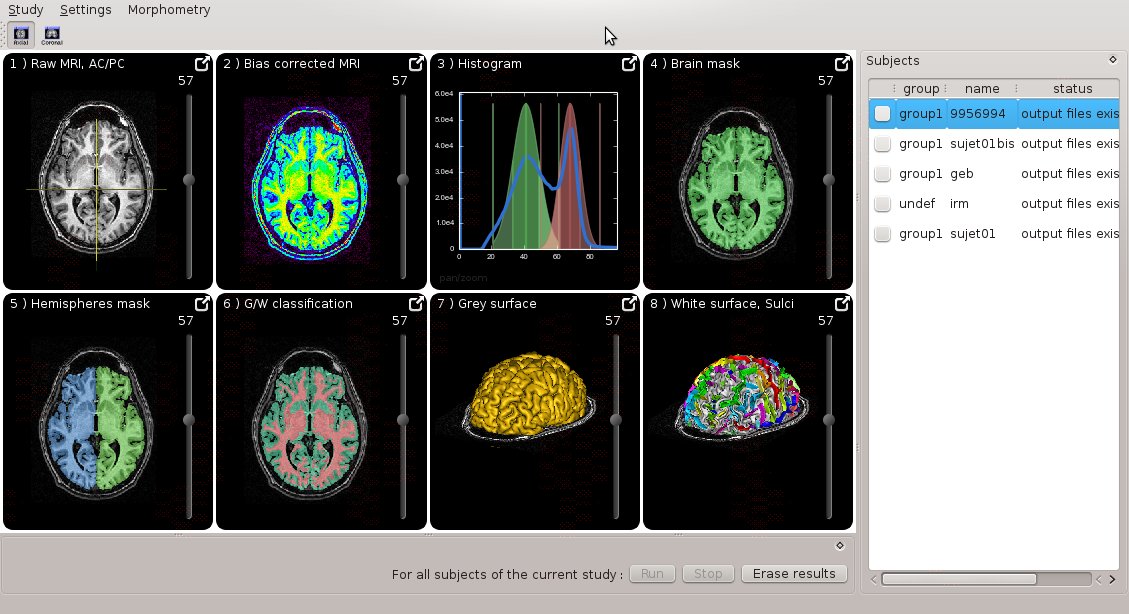

Morphologist UI¶

Morphologist now has a new graphical interface, featuring simplified user experience and quick interactive visualization:

Docmentation can be found here

It can be run either as a standalone program (morphologist), or through BrainVISA.